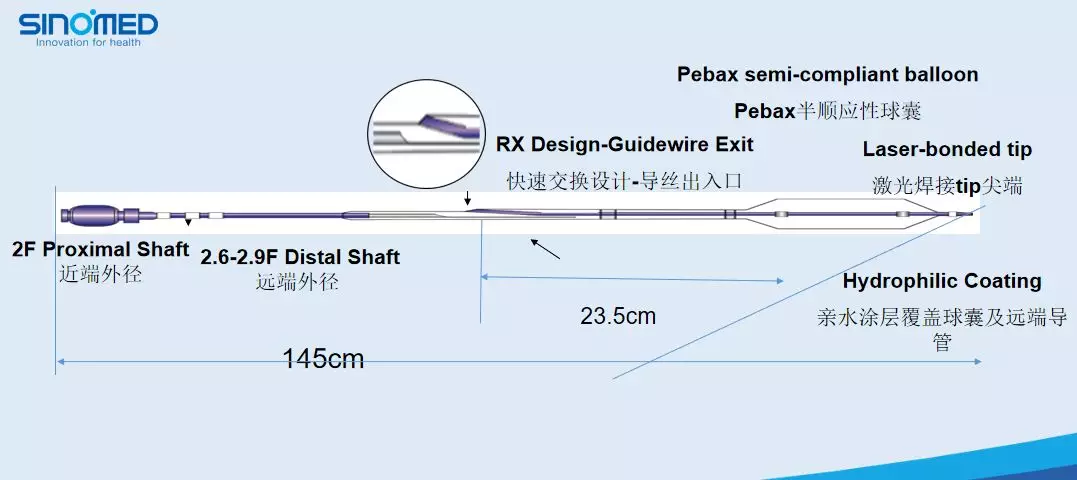

赛诺 2.0*15mm球囊扩张

赛诺 2.0*15mm球囊扩张